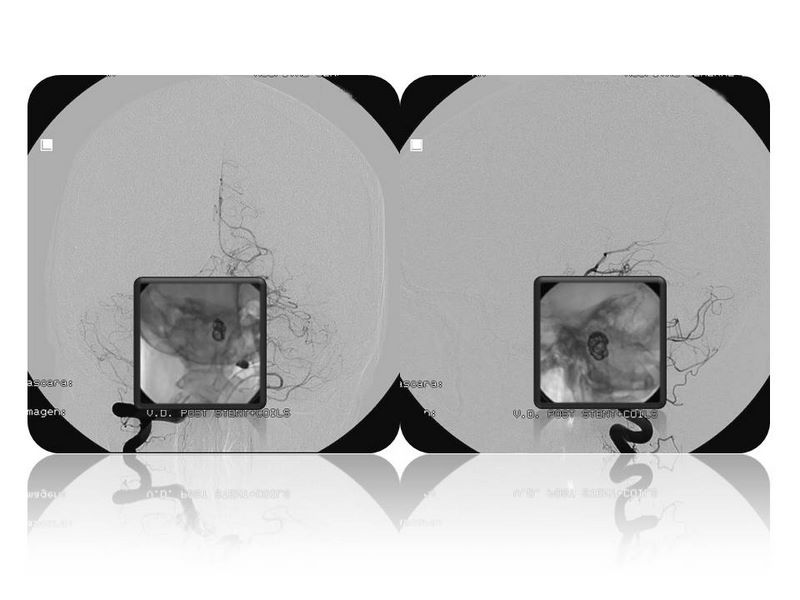

Aneurismas grandes